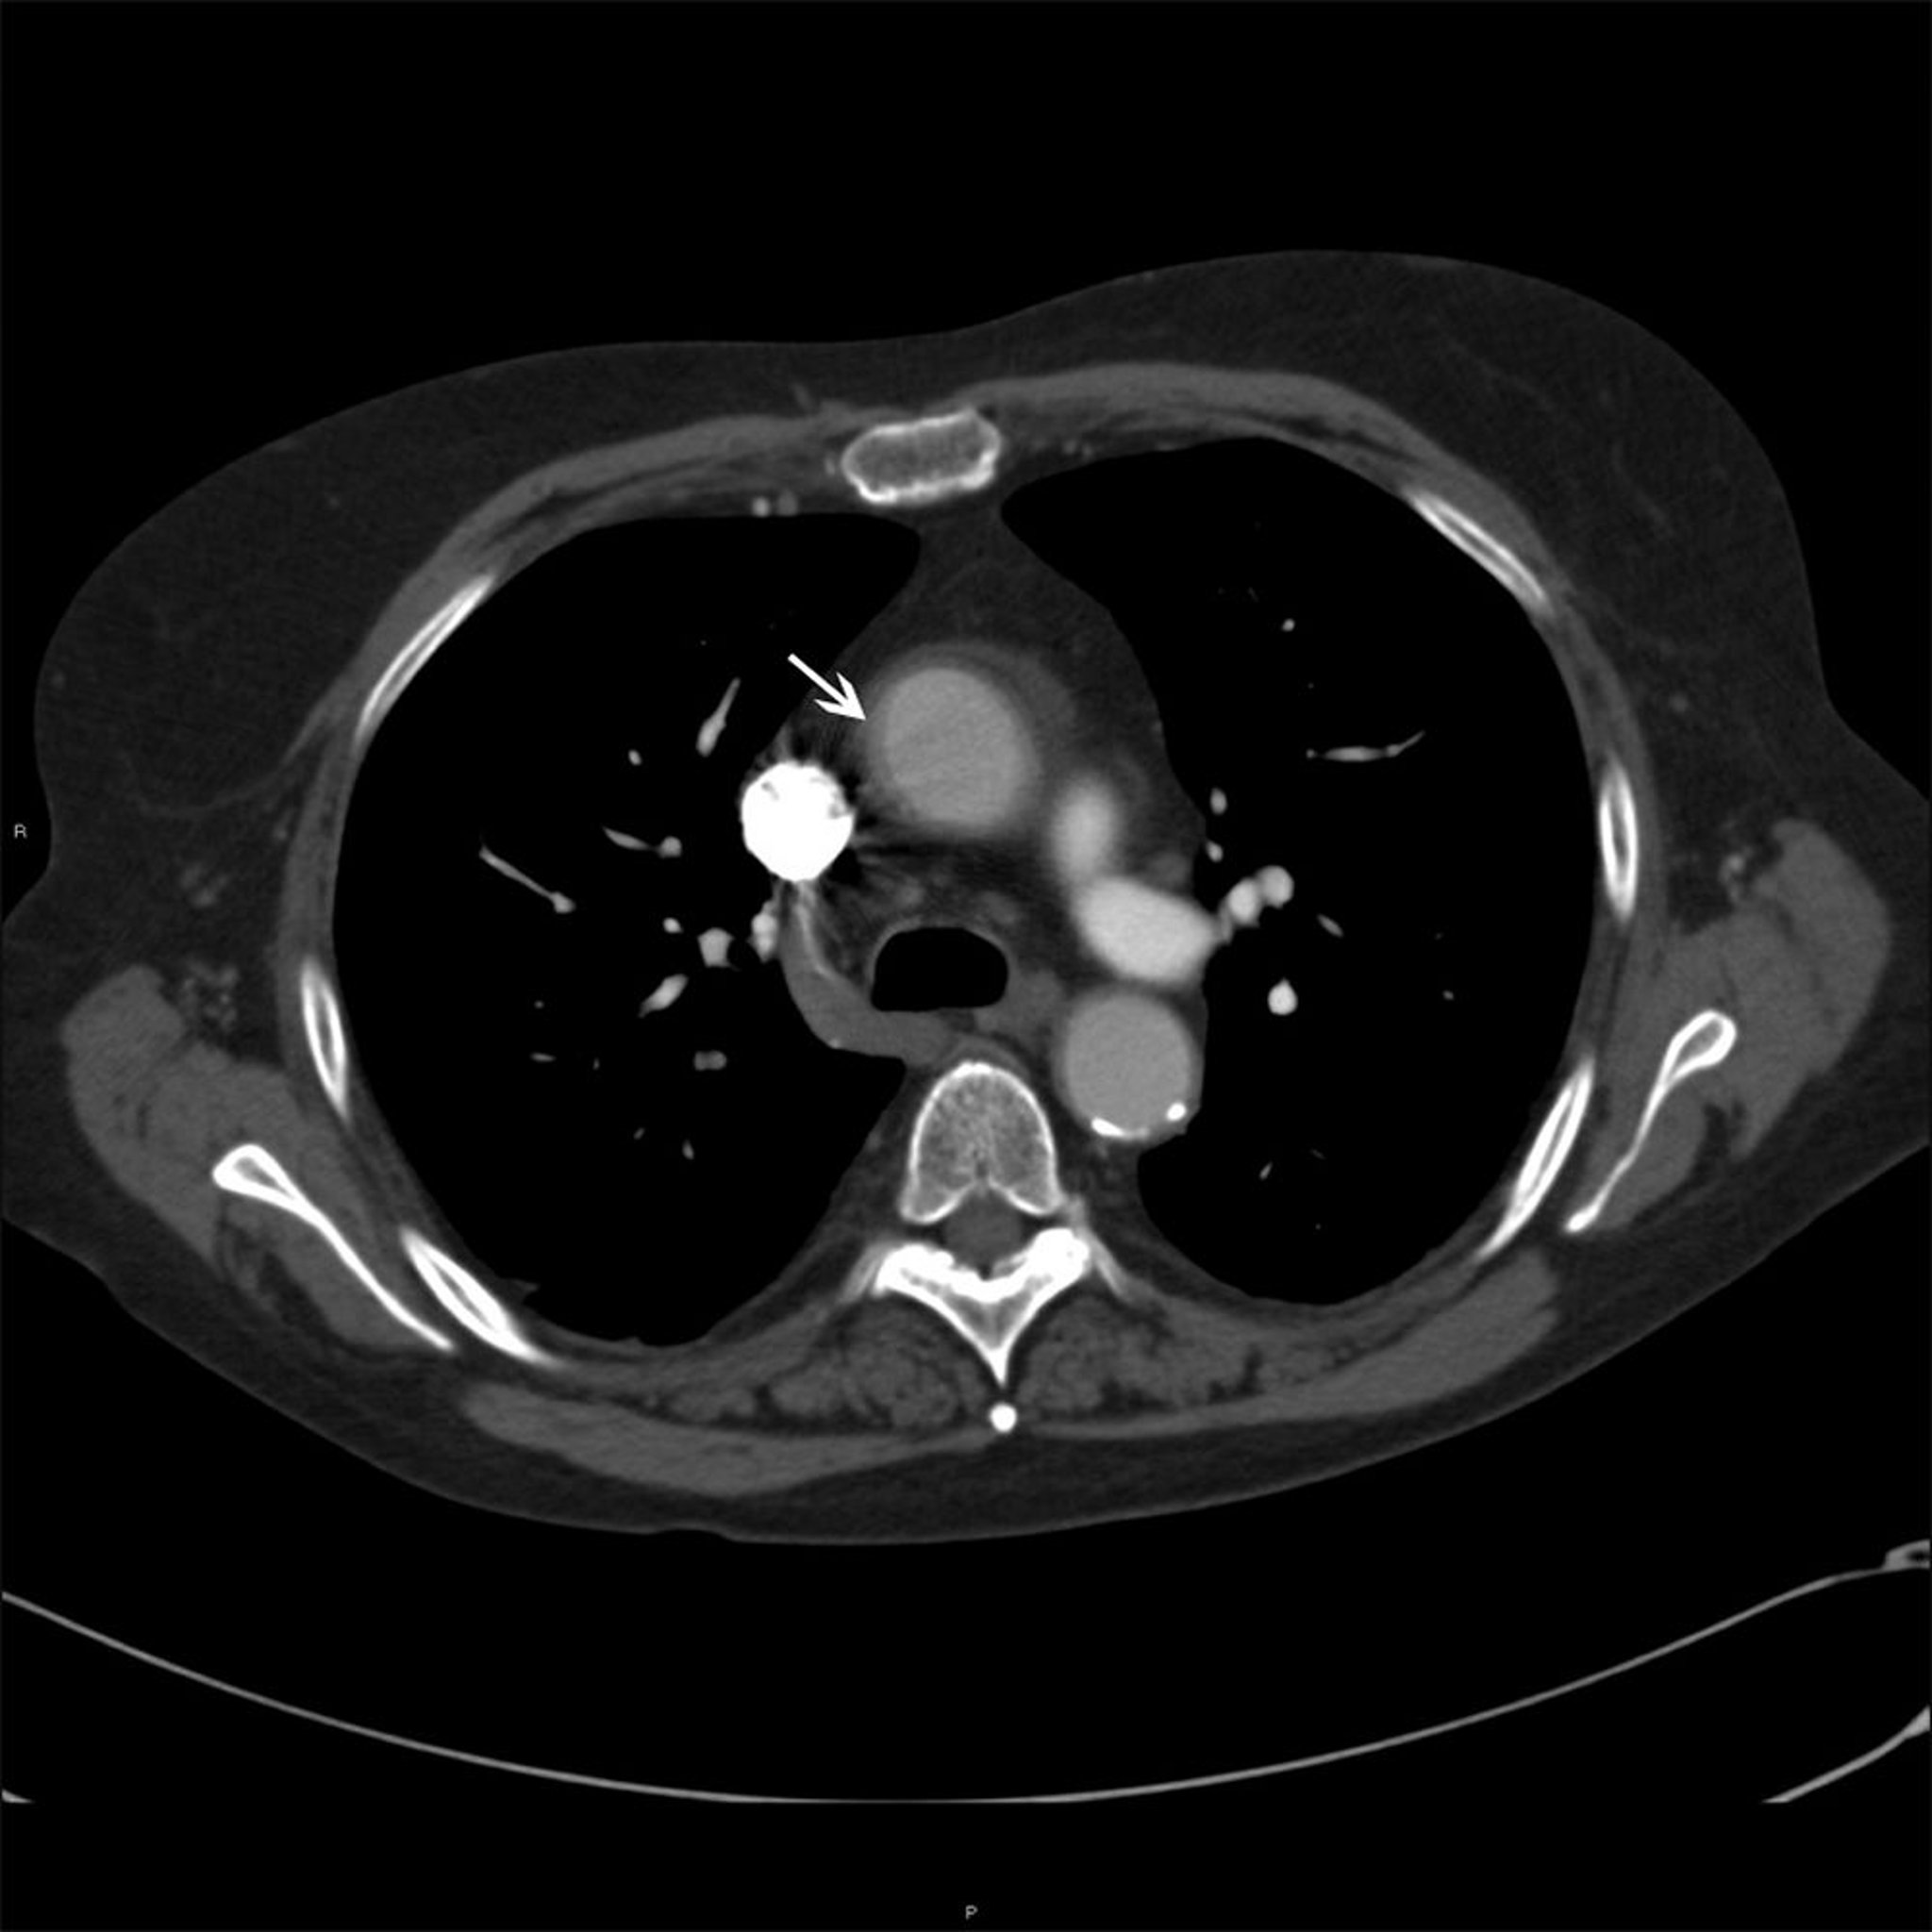

Aorta ascendente em um paciente com arterite de Takayasu

Esta foto mostra o espessamento mural (seta branca) da aorta ascendente em um paciente com arterite de Takayasu.